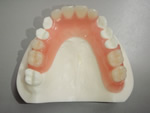

◆総入れ歯

当院の総入れ歯では、リンガライズド・オクルージョンという特別な噛み合わせで製作しております。この噛み合わせの特徴は、小さな力で食品を破砕することが可能となり、顎堤が吸収して食事中、入れ歯の安定が悪い方にお勧めです。

総入れ歯1

総入れ歯2

総入れ歯3